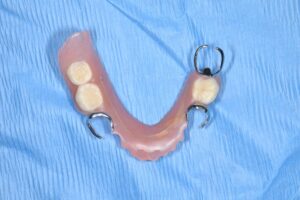

まずは初診時の写真、レントゲンです。

【初診時】

上記のように、入れ歯を長年使用されておりましたが、右下の歯が痛くて噛めないとのお悩みを抱えていらっしゃいました。